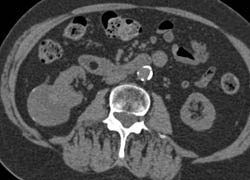

Complex Right Renal Cyst With Calcification